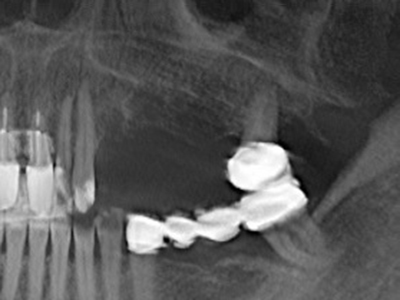

Die Präparation des lateralen Fensters bei der externen Sinusbodenelevation stellt gerade für chirurgisch unerfahrene Implantologen eine große Herausforderung dar. Die knöcherne Bedeckung der Kieferhöhle ohne eine Verletzung der darunterliegenden Schneider’schen Membran abzutragen ist dabei nur ein Teil der Operation – nach Schaffung eines ausreichenden Zugangs muss die Kieferhöhlenschleimhaut vorsichtig mobilisiert werden, um Raum für das einzubringende Material bzw. die Implantate zu schaffen. In dieser Indikation ist die Piezochirurgie zweierlei hilfreich: zum einen kann durch Verwendung diamantierter Instrumente eine selektive Knochenabtragung erfolgen und die darunter liegende Schleimhaut bleibt bei vorsichtiger Vorgehensweise intakt. Zum anderen unterstützen die Ultraschallfrequenzen zusätzlich eine komplikationslose Ablösung der Schleimhaut – sie werden durch spezielle stumpfe Ansätze in den Spaltraum zwischen Schleimhaut und Kieferhöhlenboden übertragen (Cassetta, Ricci et al. 2012, Pereira, Gealh et al. 2014) (Rickert, Vissink et al. 2013). So erscheint es nicht verwunderlich, dass in aktuellen Übersichtsarbeiten über die externe Sinusbodenelevation neben der Verwendung von rauen Implantatoberflächen und dem Einsatz von Knochenersatzmaterialien auch der Einsatz von piezoelektronischen Geräten als positiv bewertet wird (Wallace, Tarnow et al. 2012).

Bei der Knochenblockentnahme zeigen sich weitere Vorteile für die Piezochirurgie: Neben der bereits beschriebenen hohen Präzision bei der Osteotomie stellt sich gerade die Verwendung der dünnen Sägespitzen als besonders materialschonend heraus. Bei der Verwendung insbesondere von Lindemannfräsen sind mit deutlich höheren Entnahmeverlusten durch die dickere Instrumentenspitze zu rechnen (Lakshmiganthan, Gokulanathan et al. 2012). Die insbesondere bei retromolar entnommenen Blocktransplantaten notwendige basale Abtrennung wird durch speziell hierfür vorgesehene rechtwinklige Sägen erleichtert, so dass die Piezochirurgie als präzises, übersichtliches und sicheres Verfahren zur retromolaren Knochenblockgewinnung angesehen wird (Happe 2007) (Abb. 1-12).